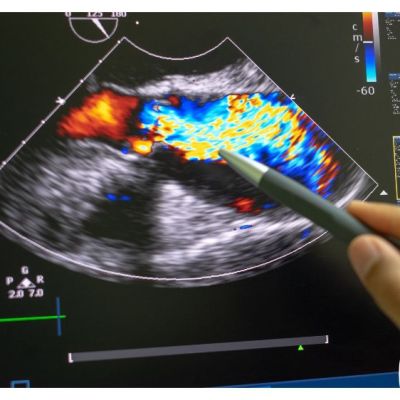

Valutazione ecocardiografica del Wall Motion Score Index

La valutazione della cinetica regionale e del Wall Motion Score Index (WMSI) è una metodologia diagnostica fondamentale per la comprensione della funzione cardiaca. Attraverso l’utilizzo di tecniche c…

Frazione di eiezione: come misurare la funzione sistolica globale

La frazione di eiezione è una misurazione della capacità di un ventricolo cardiaco di contrarsi e di espellere sangue ad ogni battito, ed è fondamentale per la valutazione della funzione sistolica glo…